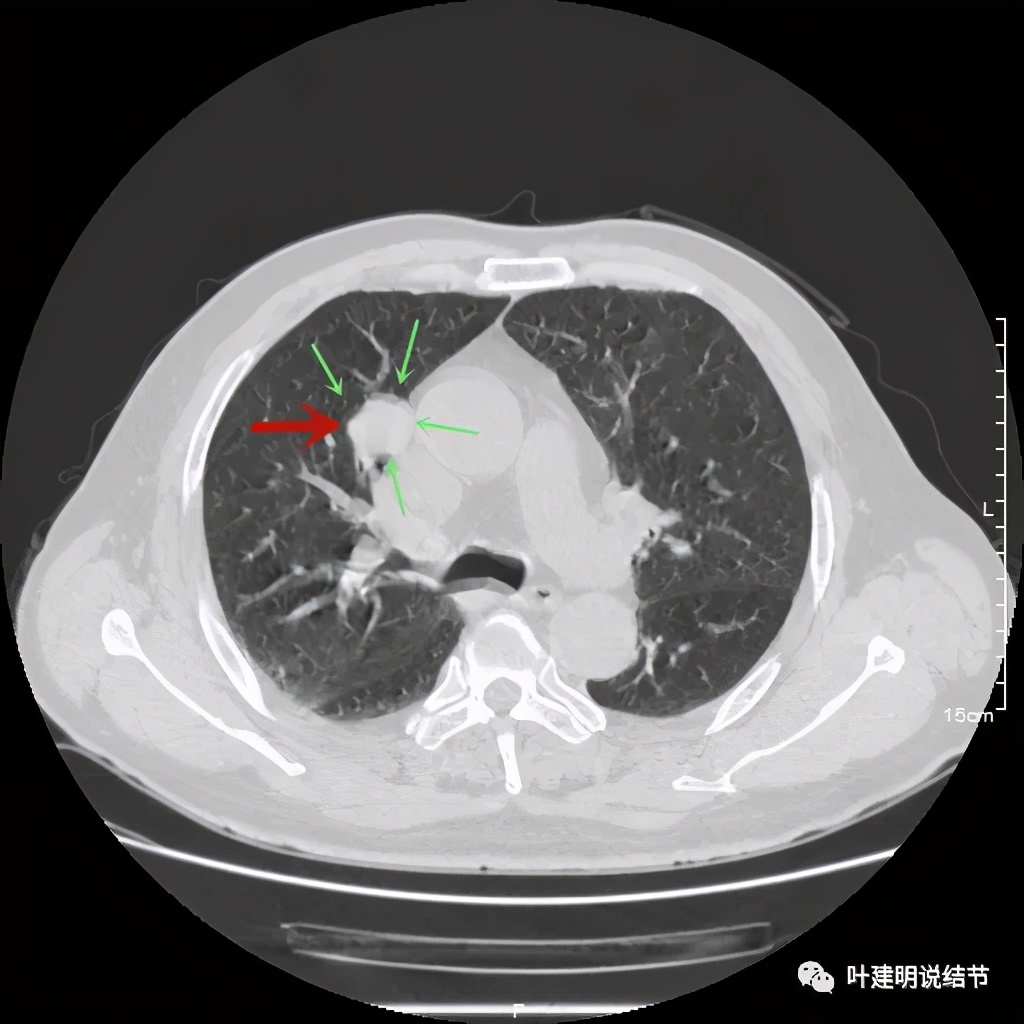

上图示病灶局部点状高密度(蓝色);边缘过于光滑(绿色)

上图示病灶密度不均,但边缘过于光滑(绿色);支气管似有截断(粉色);局部有点状钙化(蓝色)